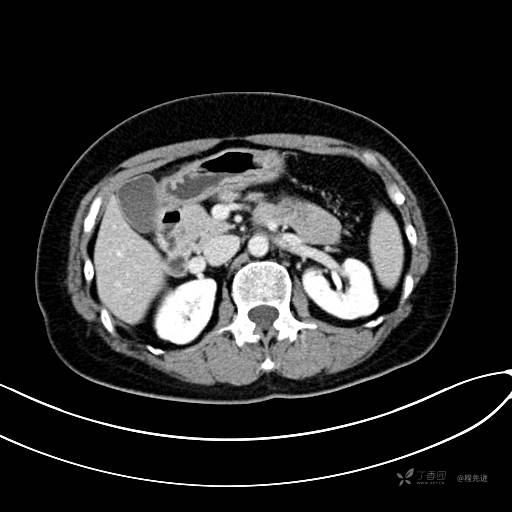

CT增强动脉期